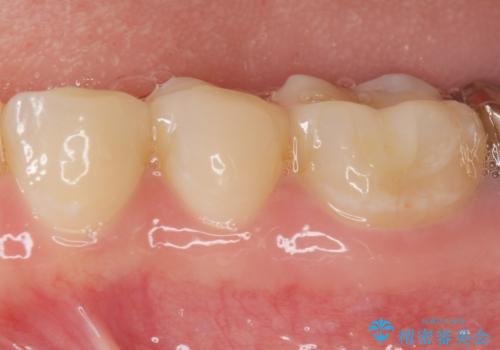

天然の歯のような色調を再現したセラミック修復処置を行ったことで口腔内の目立つ銀歯がなくなり満足いただくことができました。